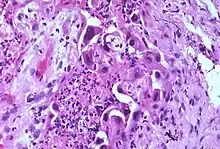

Marked atypia of type 2 pneumocytes is a characteristic finding in association with treatment with busulfan and other chemotherapeutic agents.

Atypia (from Greek, a + typos, without type; a condition of being irregular or nonstandard)[1] is a histopathologic term for a structural abnormality in a cell, i.e. it is used to describe atypical cells.